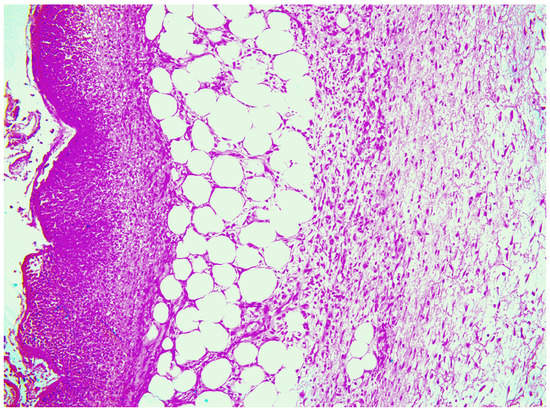

—fibrin clot,

—granulation tissue,

—adipose tissue.